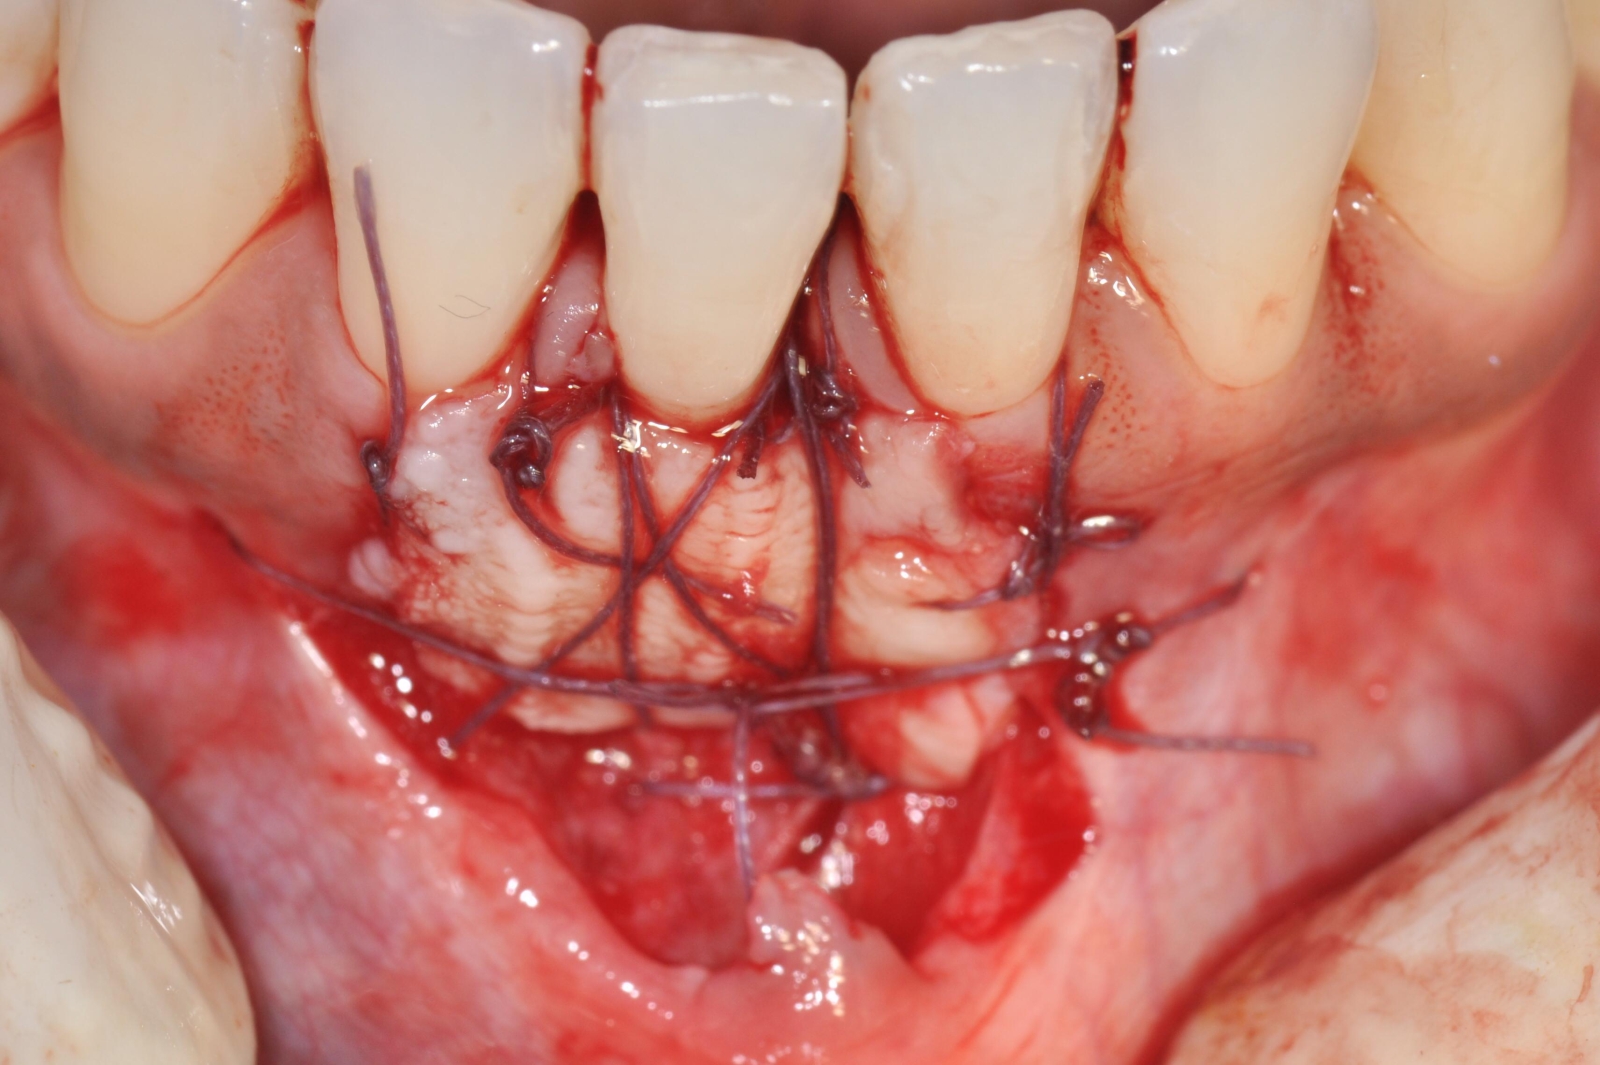

Celles-ci incluent la chirurgie à lambeaux pour un nettoyage en profondeur, la greffe gingivale ou conjonctive afin de renforcer les tissus, et la chirurgie du sourire gingival (ou "Gummy Smile") pour réharmoniser l’esthétique du sourire.

- Greffe Gingivales et conjonctives